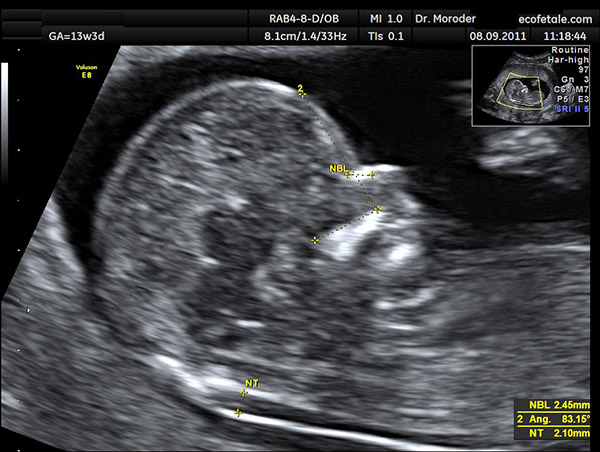

Đối với thai nhi được khoảng 11 tuần tuổi, độ mờ da gáy bình thường là 2 mm. Thai nhi 12 tuần tuổi thì độ mờ da gáy bình thường là 2.5 mm. Thai nhi bình thường sẽ có kết quả siêu âm đo độ mờ da gáy tăng dần theo tuổi thai nhưng luôn dưới 3.5 mm .

Kết quả phản ánh nguy cơ mắc bệnh

Nếu thai nhi có độ mờ da gáy trên 3.5 mm thì nên lưu ý thai nhi có nguy cơ mắc hội chứng Down. Độ mờ da gáy khoảng 6mm thì ngoài hội chứng Down, thai nhi còn có nguy cơ mắc dị tật bẩm sinh.